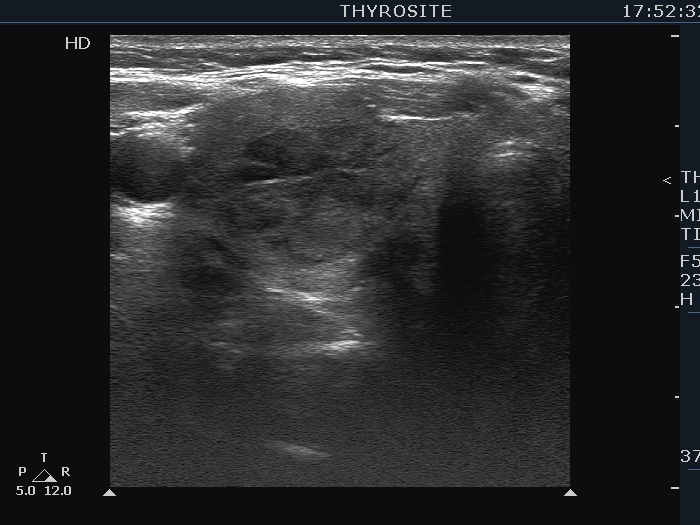

First examination (first row of images):

Clinical presentation: A 54-year-old woman was referred for an evaluation of complaints suggesting hyperthyroidism. She was treated with Graves' disease 16 years ago.

Palpation: Both lobes were enlarged and moderately firm.

Results of blood tests: hyperthyroidism (TSH undetectable, FT4 33.1 pM/L).

Ultrasonography. The thyroid was moderately hypoechoic. There was a more hypoechoic lesion in the central part of the lobe. The lesion was avascular.Aspiration cytology of the lesion resulted in benign hormonal atypia.